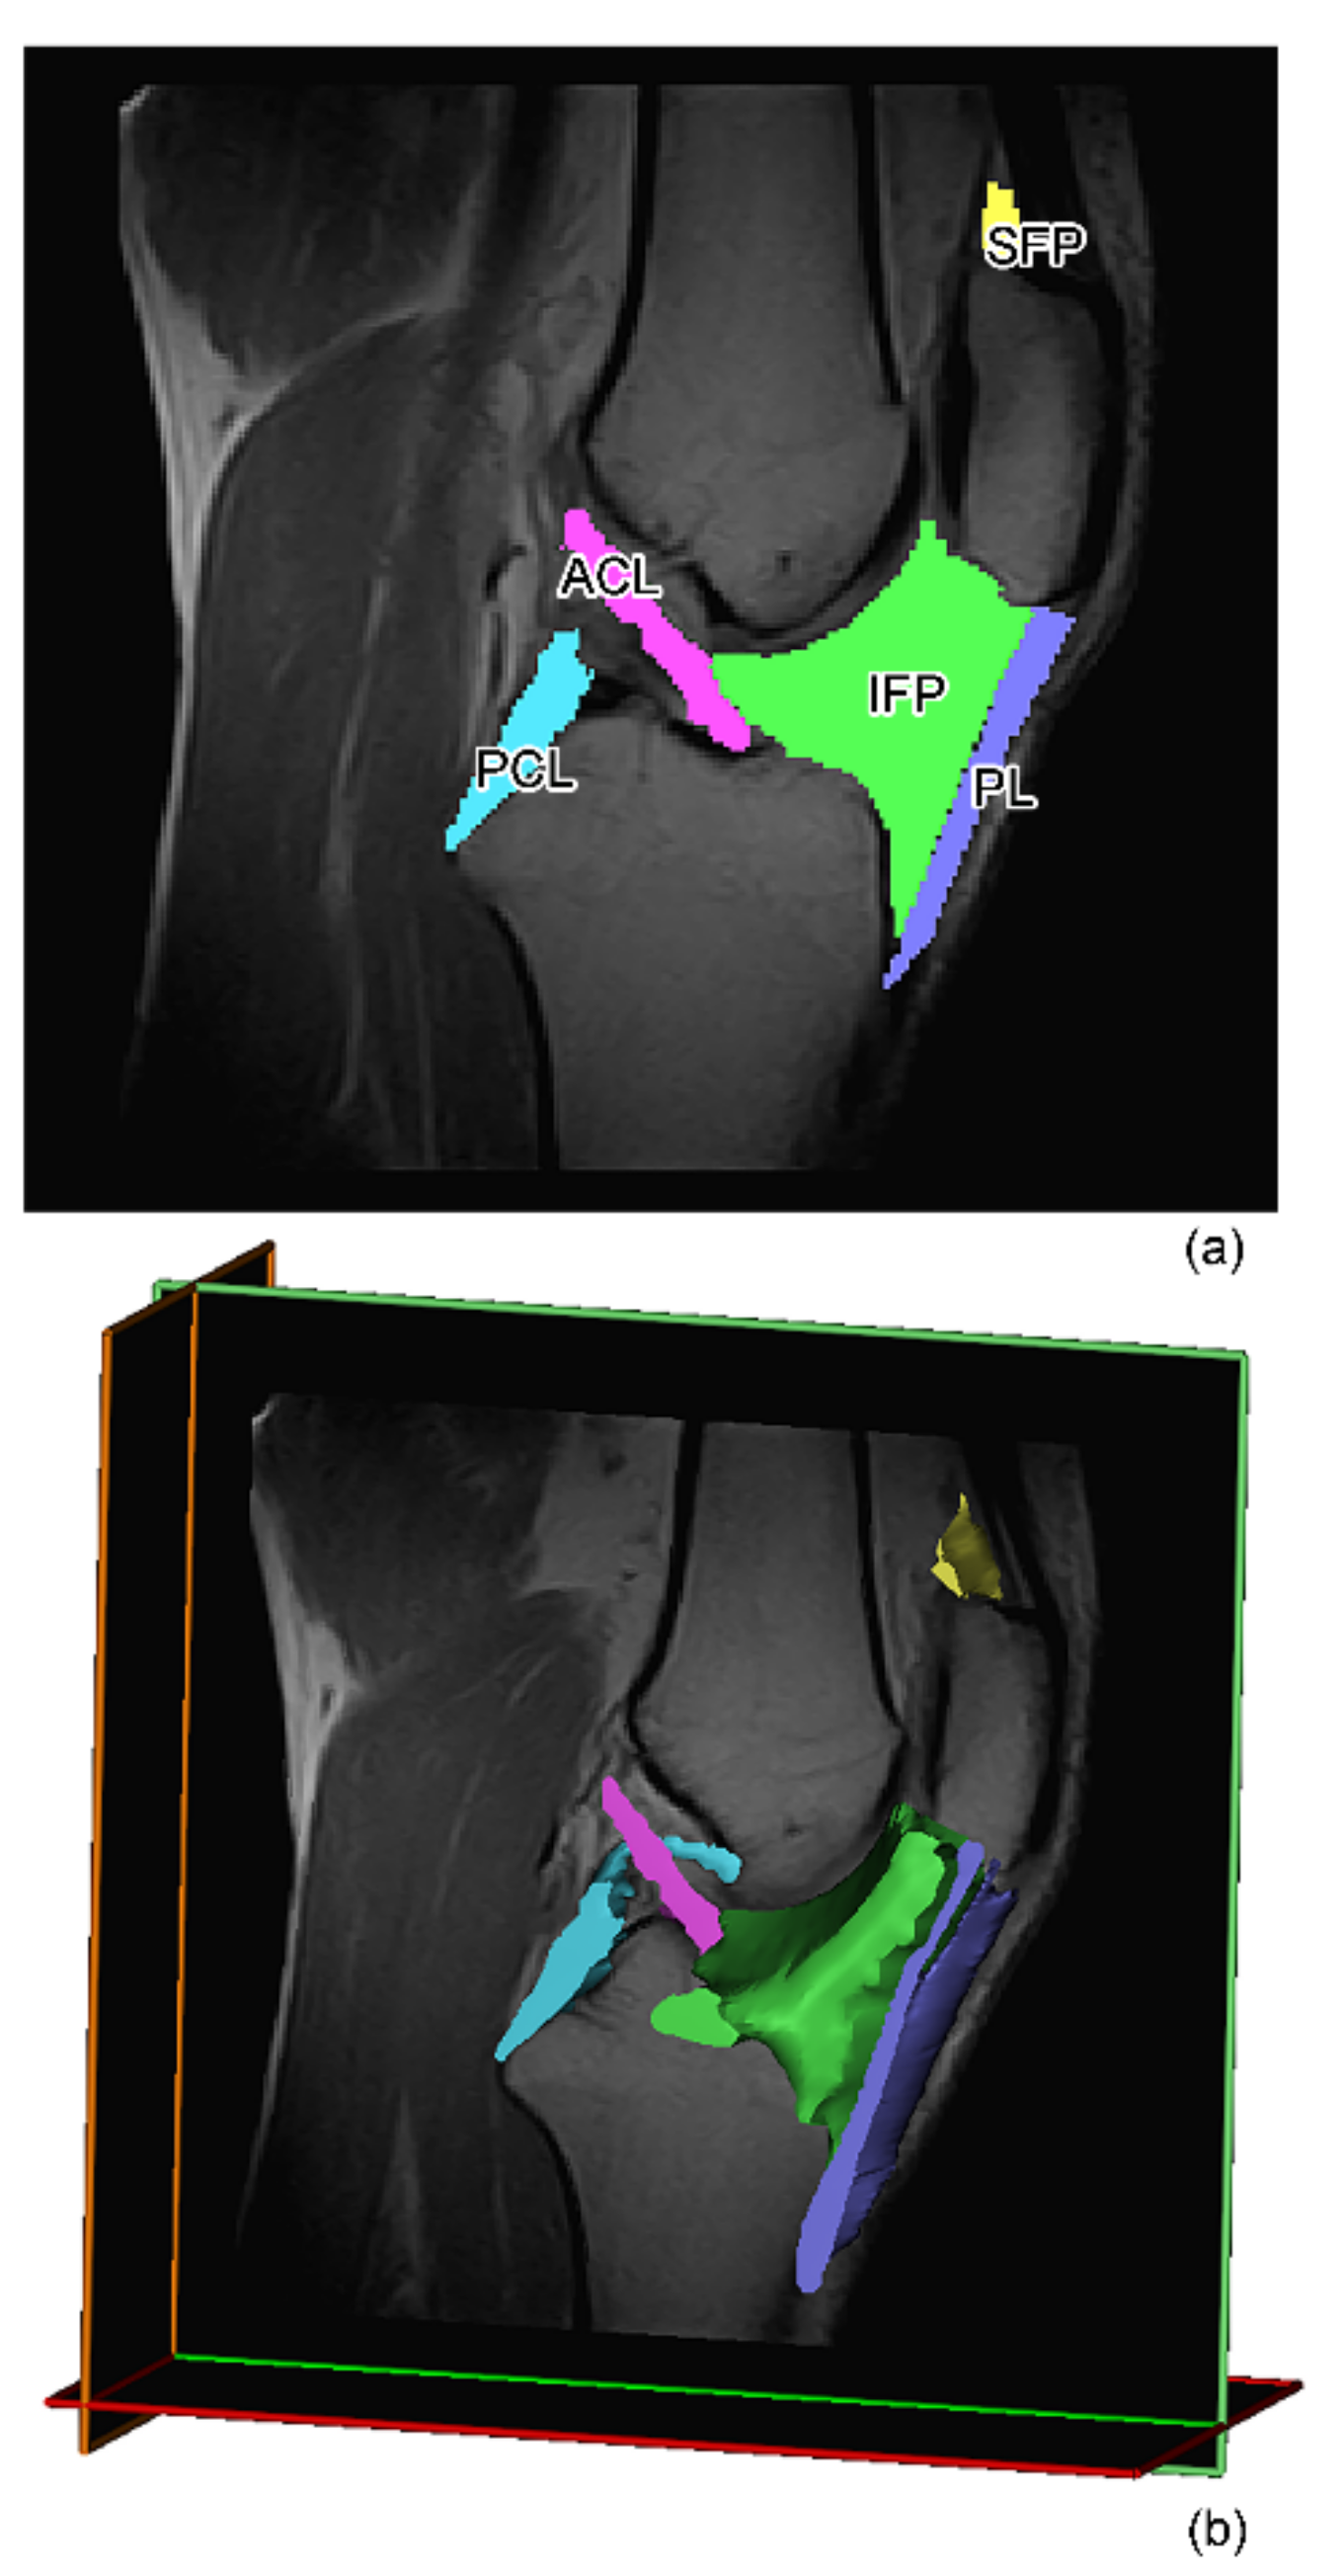

2.2. MR Image Acquisition and Analysis

Volumetric Analysis